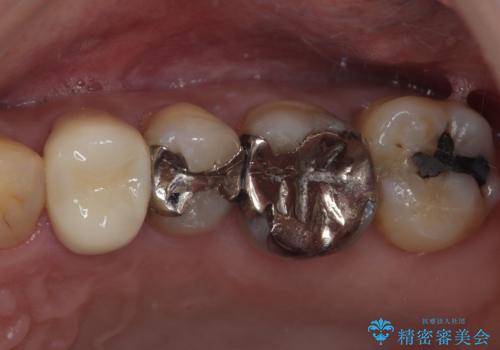

最新の症例

Latest cases